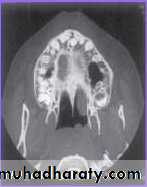

CT Scan

By Ericson & Kurol Used to diagnose the exact

position of an impacted tooth.

Clear serial radiographs may be

taken at graduated depth in any

part of human body in this

method.

This technique allows the

elimination of superimposition

of other structures.

It is however rarely used in the

diagnosis of impacted teeth

because of

(1) Large radiation dosage.

74